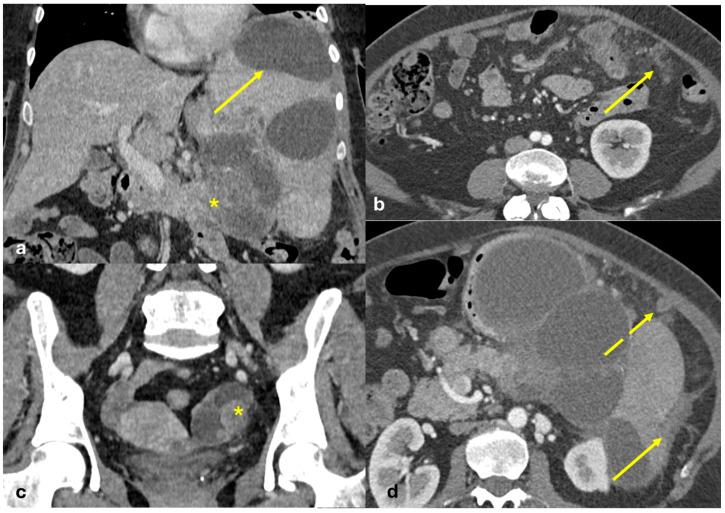

The peritoneum is a thin membrane that lines the abdominal cavity and covers the abdominal organs. It serves as a conduit for the spread of various pathological processes, including gas and fluid collections, inflammation, infections, and neoplastic conditions. Peritoneal carcinomatosis is the most common and well-known pathology involving the peritoneum, typically resulting from the dissemination of gastrointestinal and pelvic malignancies. However, numerous benign and malignant peritoneal diseases can mimic the imaging appearance of peritoneal carcinomatosis. The aim of this review is to revisit the anatomy of peritoneal compartments and elucidate the patterns of peritoneal disease spread. Emphasis is placed on identifying the distinctive imaging features of both neoplastic and non-neoplastic peritoneal diseases that differ from peritoneal carcinomatosis.

腹膜是一层薄的膜,它衬于腹腔内并覆盖腹部器官。它是各种病理过程扩散的通道,包括气体和液体聚集、炎症、感染及肿瘤性疾病。腹膜癌病是涉及腹膜的最常见且广为人知的病理情况,通常由胃肠道和盆腔恶性肿瘤的播散引起。然而,许多良性和恶性腹膜疾病可模仿腹膜癌病的影像学表现。本综述的目的是重新审视腹膜腔室的解剖结构并阐明腹膜疾病的扩散模式。重点在于识别与腹膜癌病不同的肿瘤性和非肿瘤性腹膜疾病的独特影像学特征。